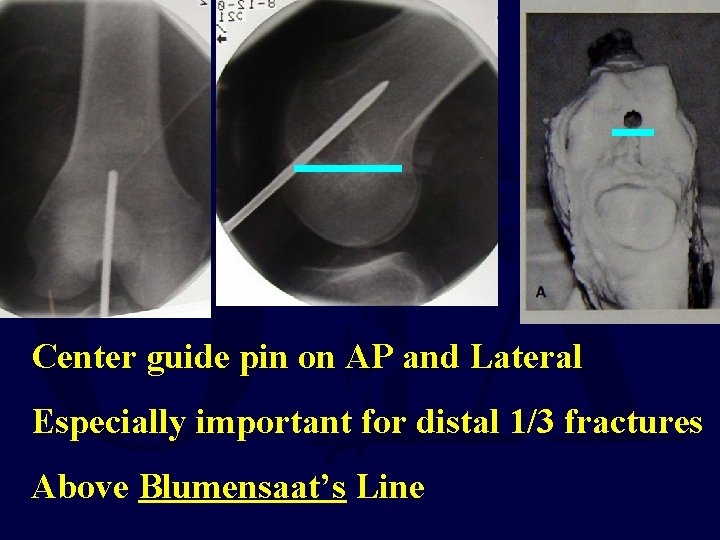

Femur Fracture Technique • Retrograde Intramedullary Nailing – Supine - flex the knee 50° to allow access to Blumensaat’s line Percutaneous with fluoro OR Limited open technique

Center guide pin on AP and Lateral Especially important for distal 1/3 fractures Above Blumensaat’s Line

Retrograde Femoral Nailing Starting Point